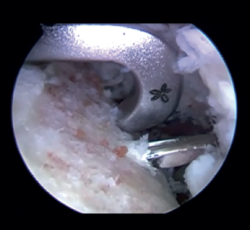

Preparation of the joint (Figure 1)

The patient is placed in lateral decubitus or beach chair position, depending on the preferences of the surgeon. A complete arthroscopic exploration is made through three standard portals, and the lesions are identified. The labrum and anterior capsule are then detached from the 2 to the 6 o'clock position, taking care to preserve their continuity. It is important to perform carefully detach labrum from the glenoid rim and remove all soft tissue until de muscle fibres of the subscapularis muscle and base of the coracoid are visualised. This will make easier the introduction of the graft and the creation of a flat bony surface to accommodate the graft.

Figure 1. View from the anterosuperior portal (left shoulder). Note the flat glenoid surface after drilling and roughening of the glenoid bed and deinsertion of the anteroinferior capsulolabral complex.

We then address the bone defect: with the glenoid defect exposed, the defect is evened, with drilling and roughening of the glenoid cavity neck until a flat and uniform surface is obtained on which to position the graft. The central point of the defect is selected for positioning of the graft, and an implant is inserted as a reference that subsequently will be used for capsulolabral repair.